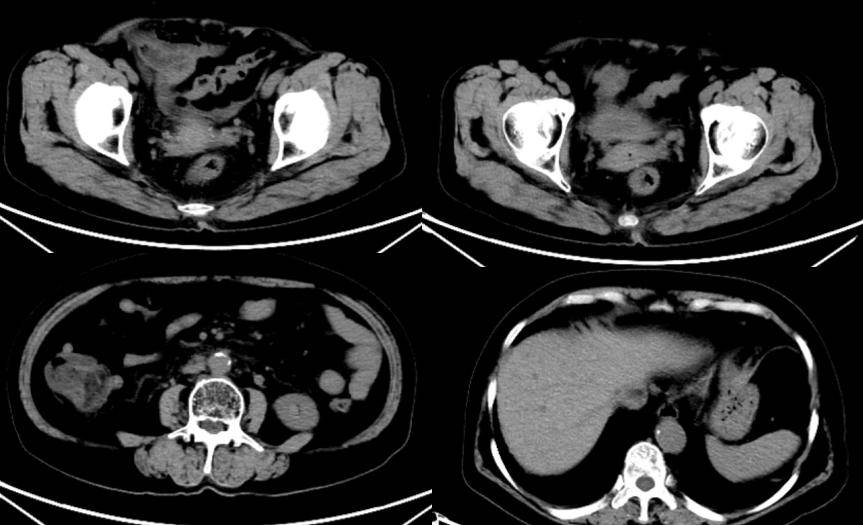

疗效评估:2025年3月13日复旦大学附属肿瘤医院PET-CT提示:直肠癌治疗后,直肠和乙状结肠条索状FDG代谢增高,建议结合肠镜,腹膜后、双侧髂血管旁和腹股沟区小淋巴结,未见明显FDG代谢增高。疗效评估为完全缓解(CR)。

腹膜后淋巴结消失,既往考虑转移(?)。MDT再次讨论,诊断修正为:直肠腺癌 cT3N2aM1 IVA期。